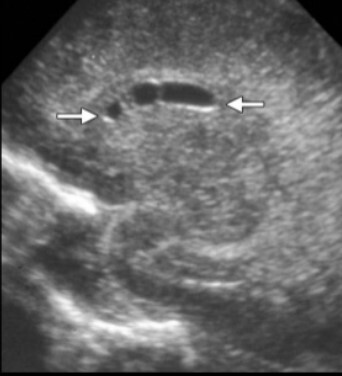

Neonatology Cyst 2 Image